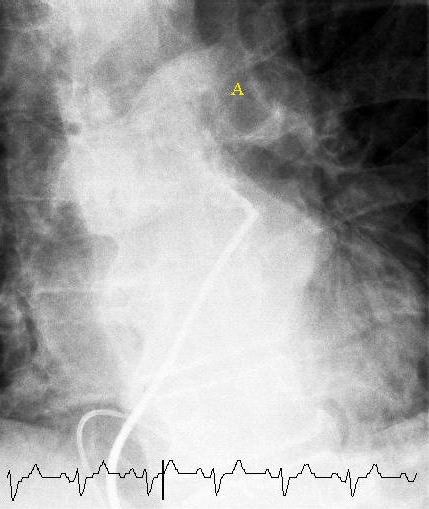

선택적 폐 혈관 조영술로, 왼쪽 주 폐동맥에서 중앙 폐색을 일으키는 혈전(A로 표시)을 보여준다. 심전도 추적은 하단에 표시됩니다.

과거 진단의 골드 스탠다드는 투시경 검사를 이용한 폐 혈관 조영술이었으나, 비침습적 기술 발달로 사용이 감소했다.[67]